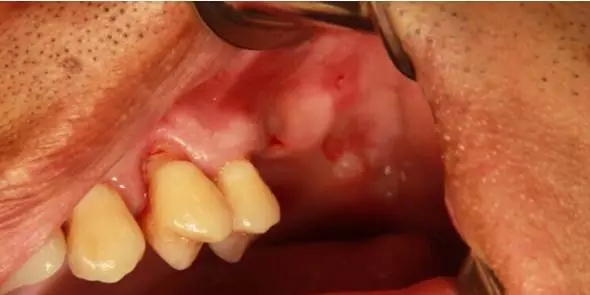

患者50歲,男性,身體健康。左上6,7缺失,骨高度2mm。

術(shù)前口內(nèi)照和CT片。

因為4,5根方要取骨,所以切口設計在4的近中。